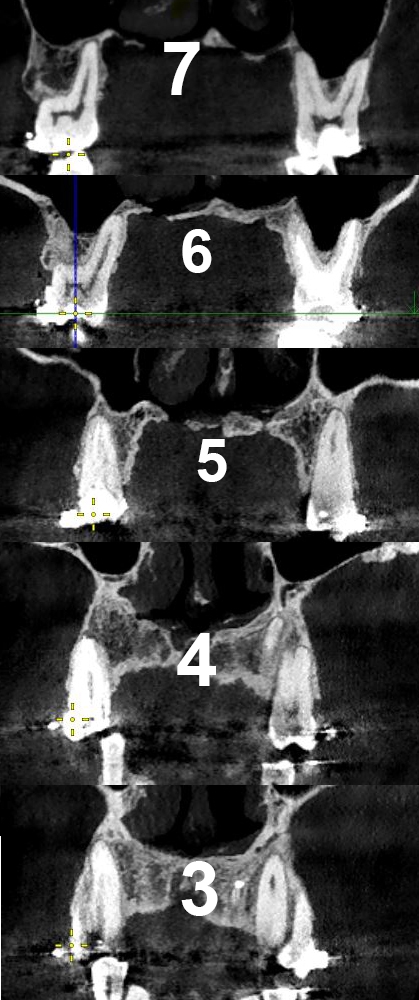

>>1607542

>Киста внутри зуба, в канале?

нет, киста за пределами зуба на конце корня. Происходит из-за того что в канале инфекция, она выходит за пределы зуба в кость образуя очаг воспаления, который организм изолирует фиброзной тканью.

>Как то ощущалась вообще?

В большинстве случаев - хронический периодонтит никак себя не проявляет, может годами быть и пидарнуть при ослаблении иммунитета, может произойти дренаж содержимого через десну - т.н. свищ - что-то типа белого прыща на десне, может так же ощущаться при надавливании в области дислокации. Реактивный периодонтит - обычно вызывает, боль, отек, температуру - то что обычно называют флюсом.

>Как обнаружили кисту эту?

Сделать рентген или КТ.